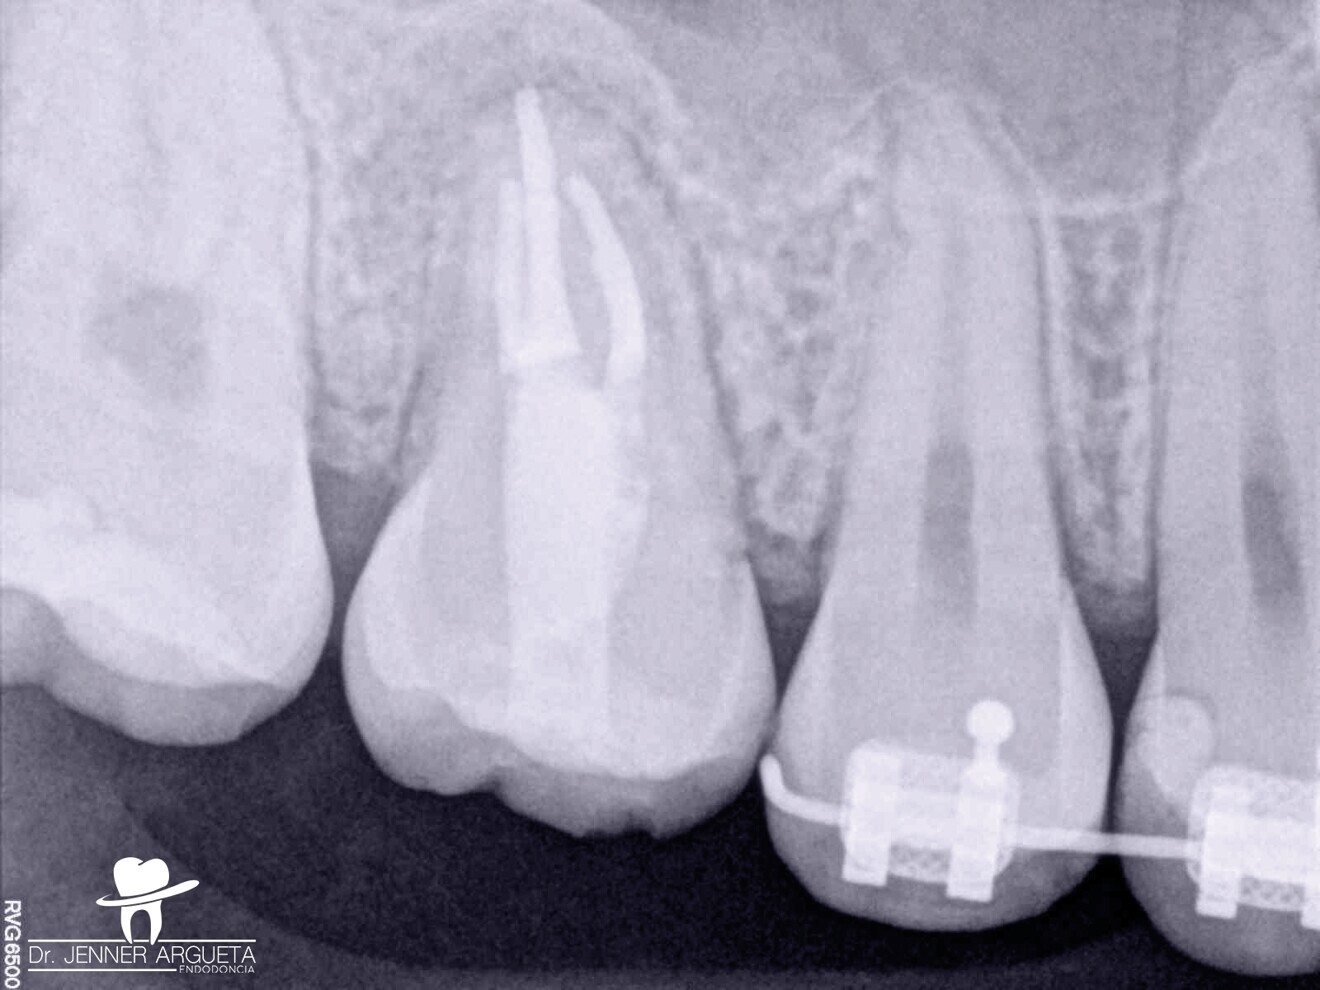

Première molaire maxillaire fortement endommagée, restaurée avec un ancien amalgame après un traitement endocanalaire, et présentant des caries récurrentes. (Photo : Jenner Argueta)

Une patiente de 16 ans a consulté le cabinet pour une évaluation de sa première molaire droite supérieure (dent 16 – Fig. 1). L’orthodontiste qui nous l’avait adressée demandait que tout soit mis en œuvre pour sauver cette dent. Le diagnostic était une parodontite périapicale symptomatique ayant déjà fait l’objet d’un traitement, et un examen minutieux a exclu toute possibilité de restauration. Avec l’accord des parents et de la patiente, nous avons pris la décision d’extraire la dent 16 et de procéder à une transplantation autogène de la dent 18 dans ce site (Fig. 2), étant donné que l’orthodontiste avait déjà prévu l’extraction de cette dent 18 et l’équilibration de l’occlusion de la patiente à la fin du traitement orthodontique. Les dents n 16 et 18 ont été extraites de la manière la moins traumatique possible. Après un remodelage osseux mineur de l’alvéole à l’aide de fraises à basse vitesse, la troisième molaire a été transplantée dans l’alvéole receveuse (Fig. 3). Une contention flexible constituée d’un monofilament de nylon a été utilisée pour maintenir la dent en place (Fig. 4). Deux semaines plus tard, la contention a été retirée, laissant des tissus mous sains et asymptomatiques et une alvéole dans laquelle la dent était stable (Figs. 5a et b).